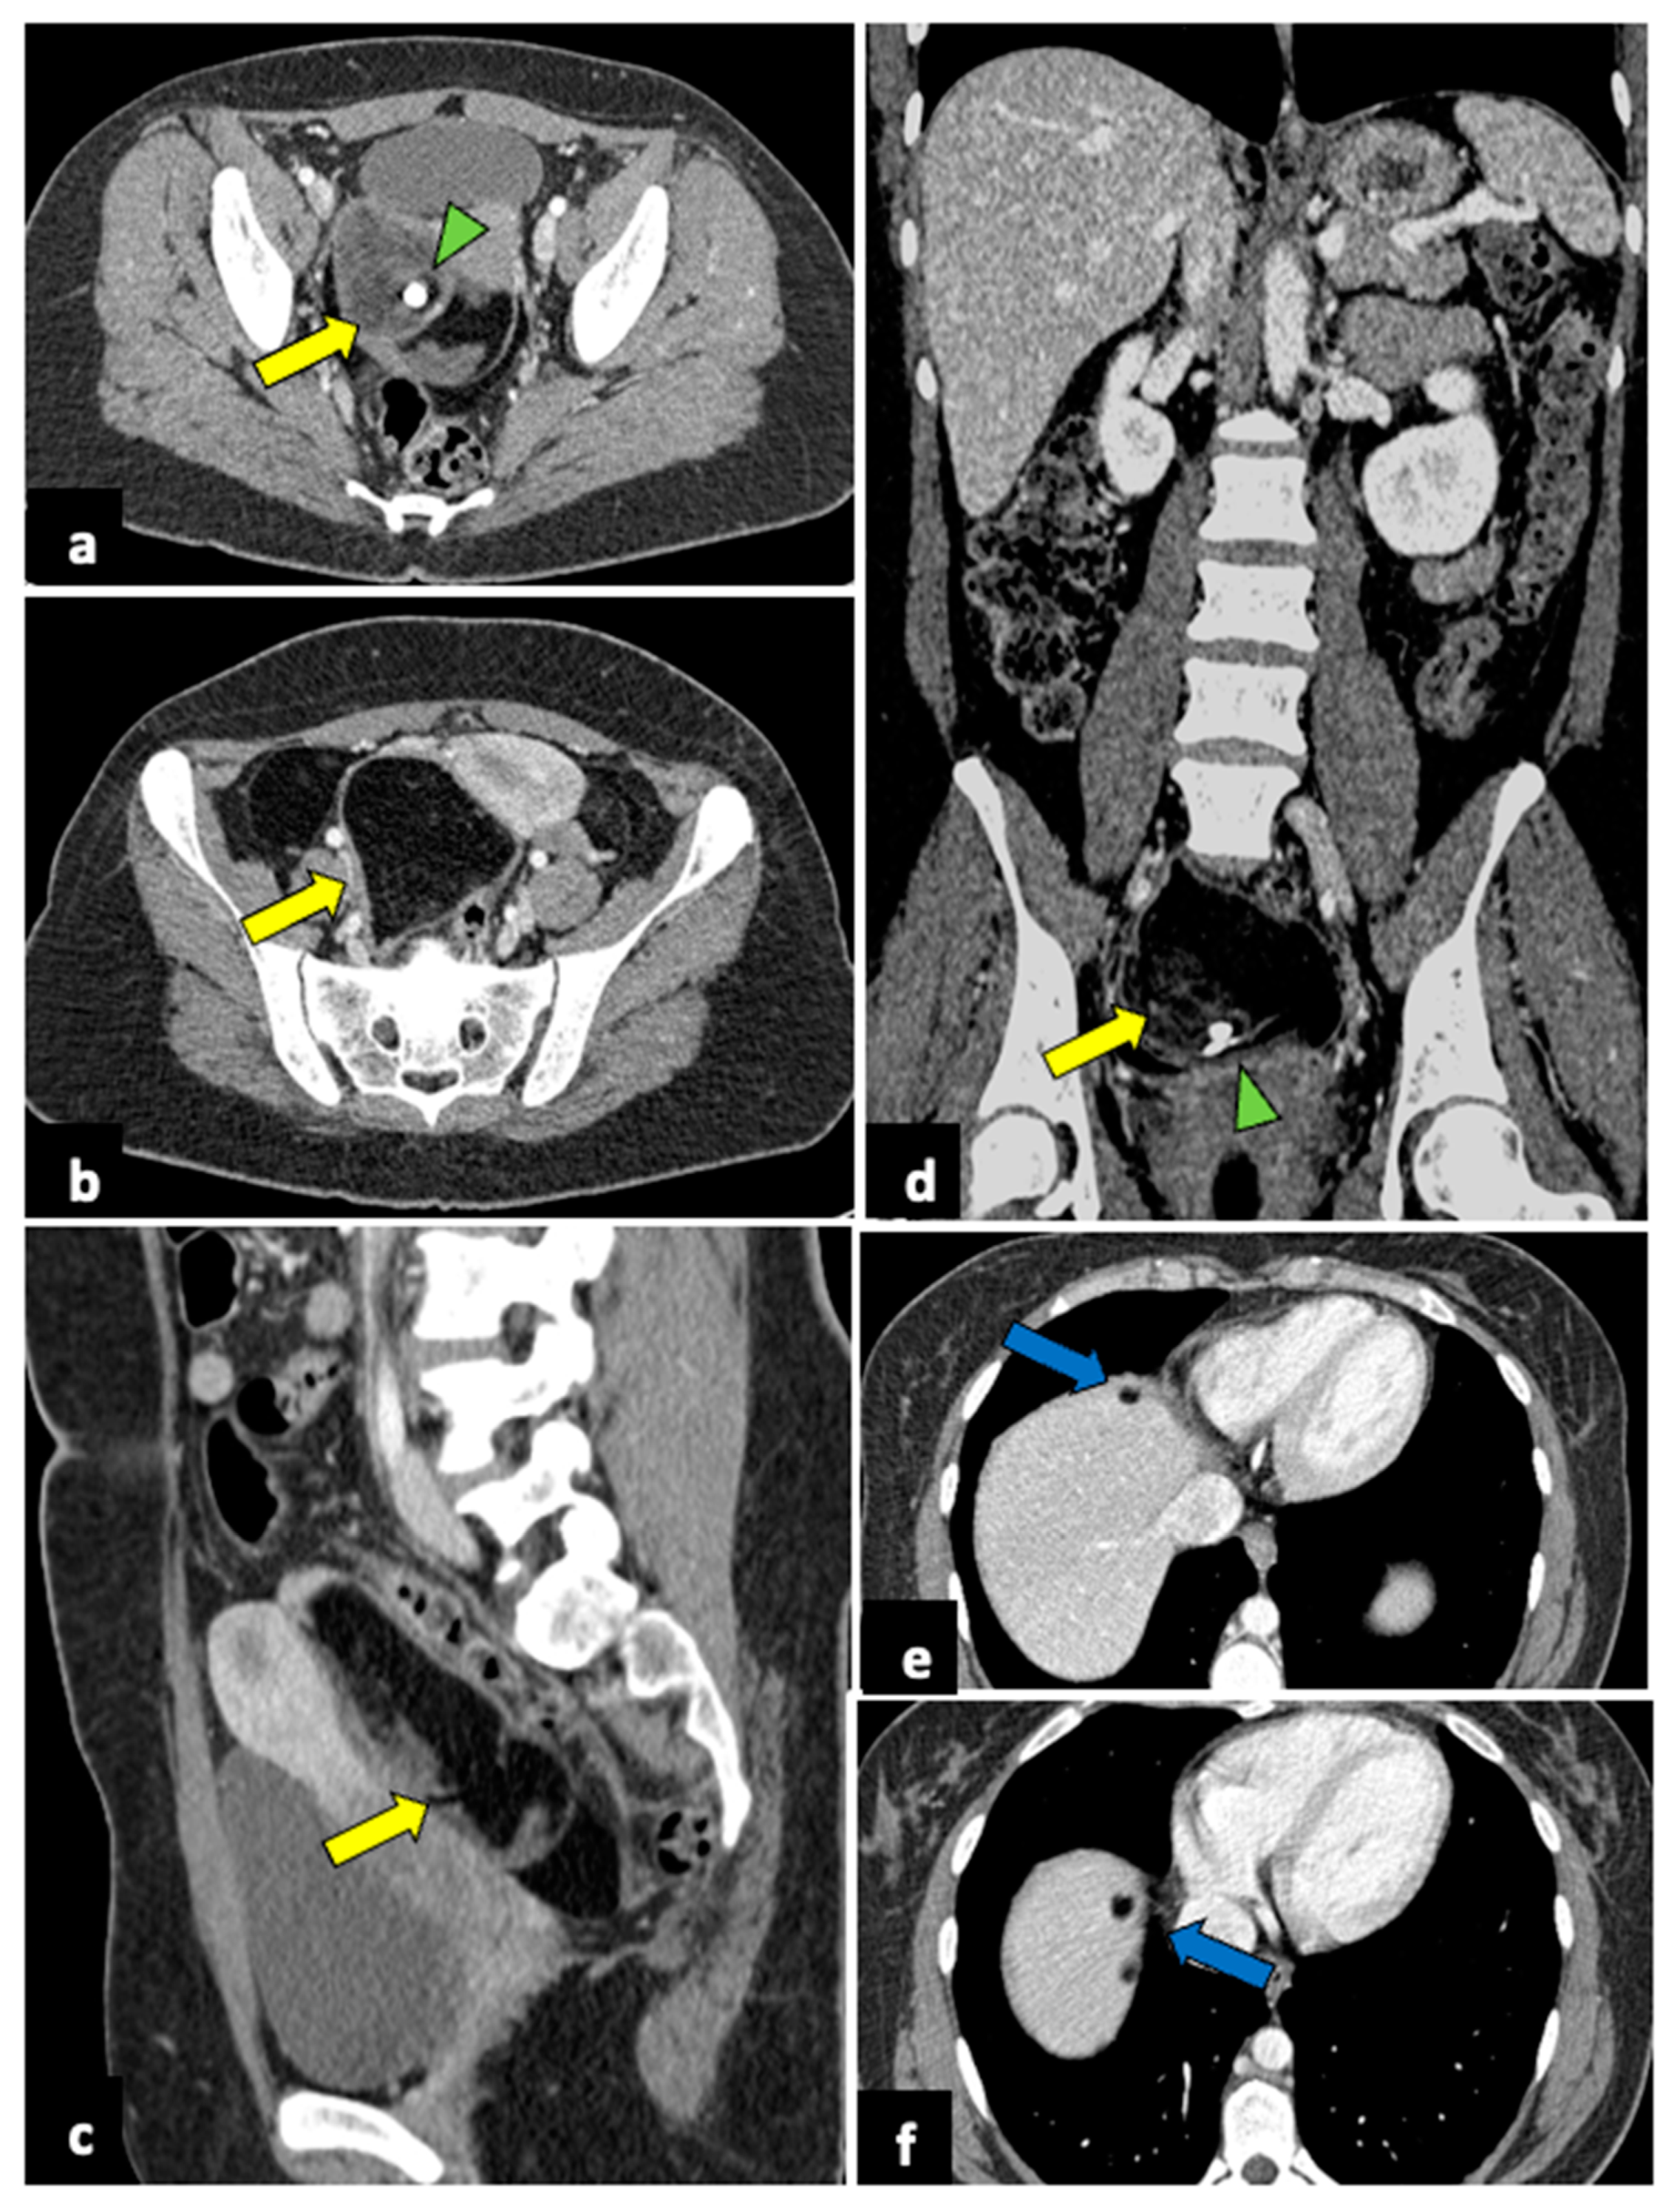

Figure 9.

Ruptured ovarian teratoma in a thirty-eight-year-old woman presenting with pelvic pain and fever. CT axial (a,b), coronal (c), and sagittal (d) planes reveal a sizeable pelvic mass (yellow arrows) composed of fat and fluid with discontinued walls (red arrow) and an interior tooth-like calcification (green arrowheads). Subphrenic fatty implants (blue arrows) are also observed (e,f). After adnexectomy, histology confirmed the diagnosis of right mature teratoma.